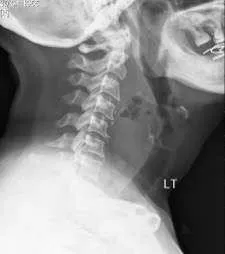

QRetropharyngeal Abscess

- Question: A 6- year- old child presented with stridor, odynophagia and fever. on examination there was bulge in the posterior pharyngeal wall, lateral X-ray shown in the picture.

- Answer:

- A- What is the most likely diagnosis?

- Retropharyngeal abscess

- B- What is the best management for this condition?

- Intra oral drainage & incision, I.V antibiotics, Airway Management

Adenoid Enlargement, ,

- Question: 3 years old came with snoring + sleep disturbance, in examination patient was mouth breather.

- Diagnosis?

- Severe Adenoid enlargement

- Whatโs the treatment?

- Conservative, Surgical: adenoidectomy